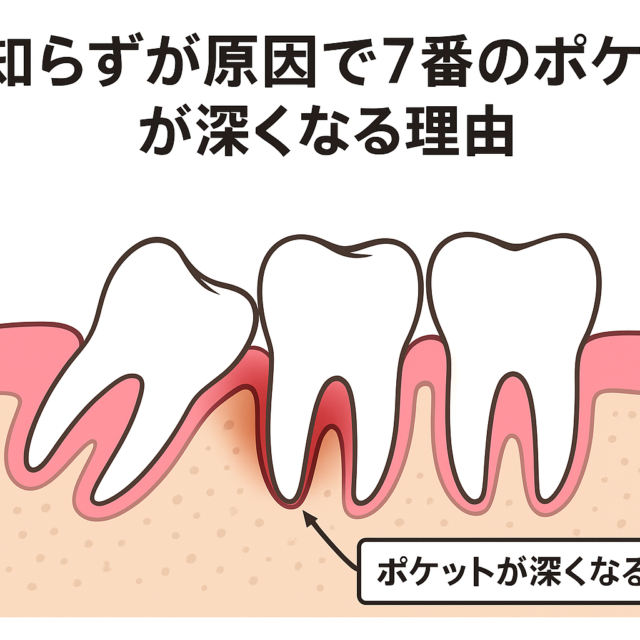

歯周病治療をするうえで、歯周ポケット内の歯石(歯肉縁下歯石)の除去はとても重要になります。